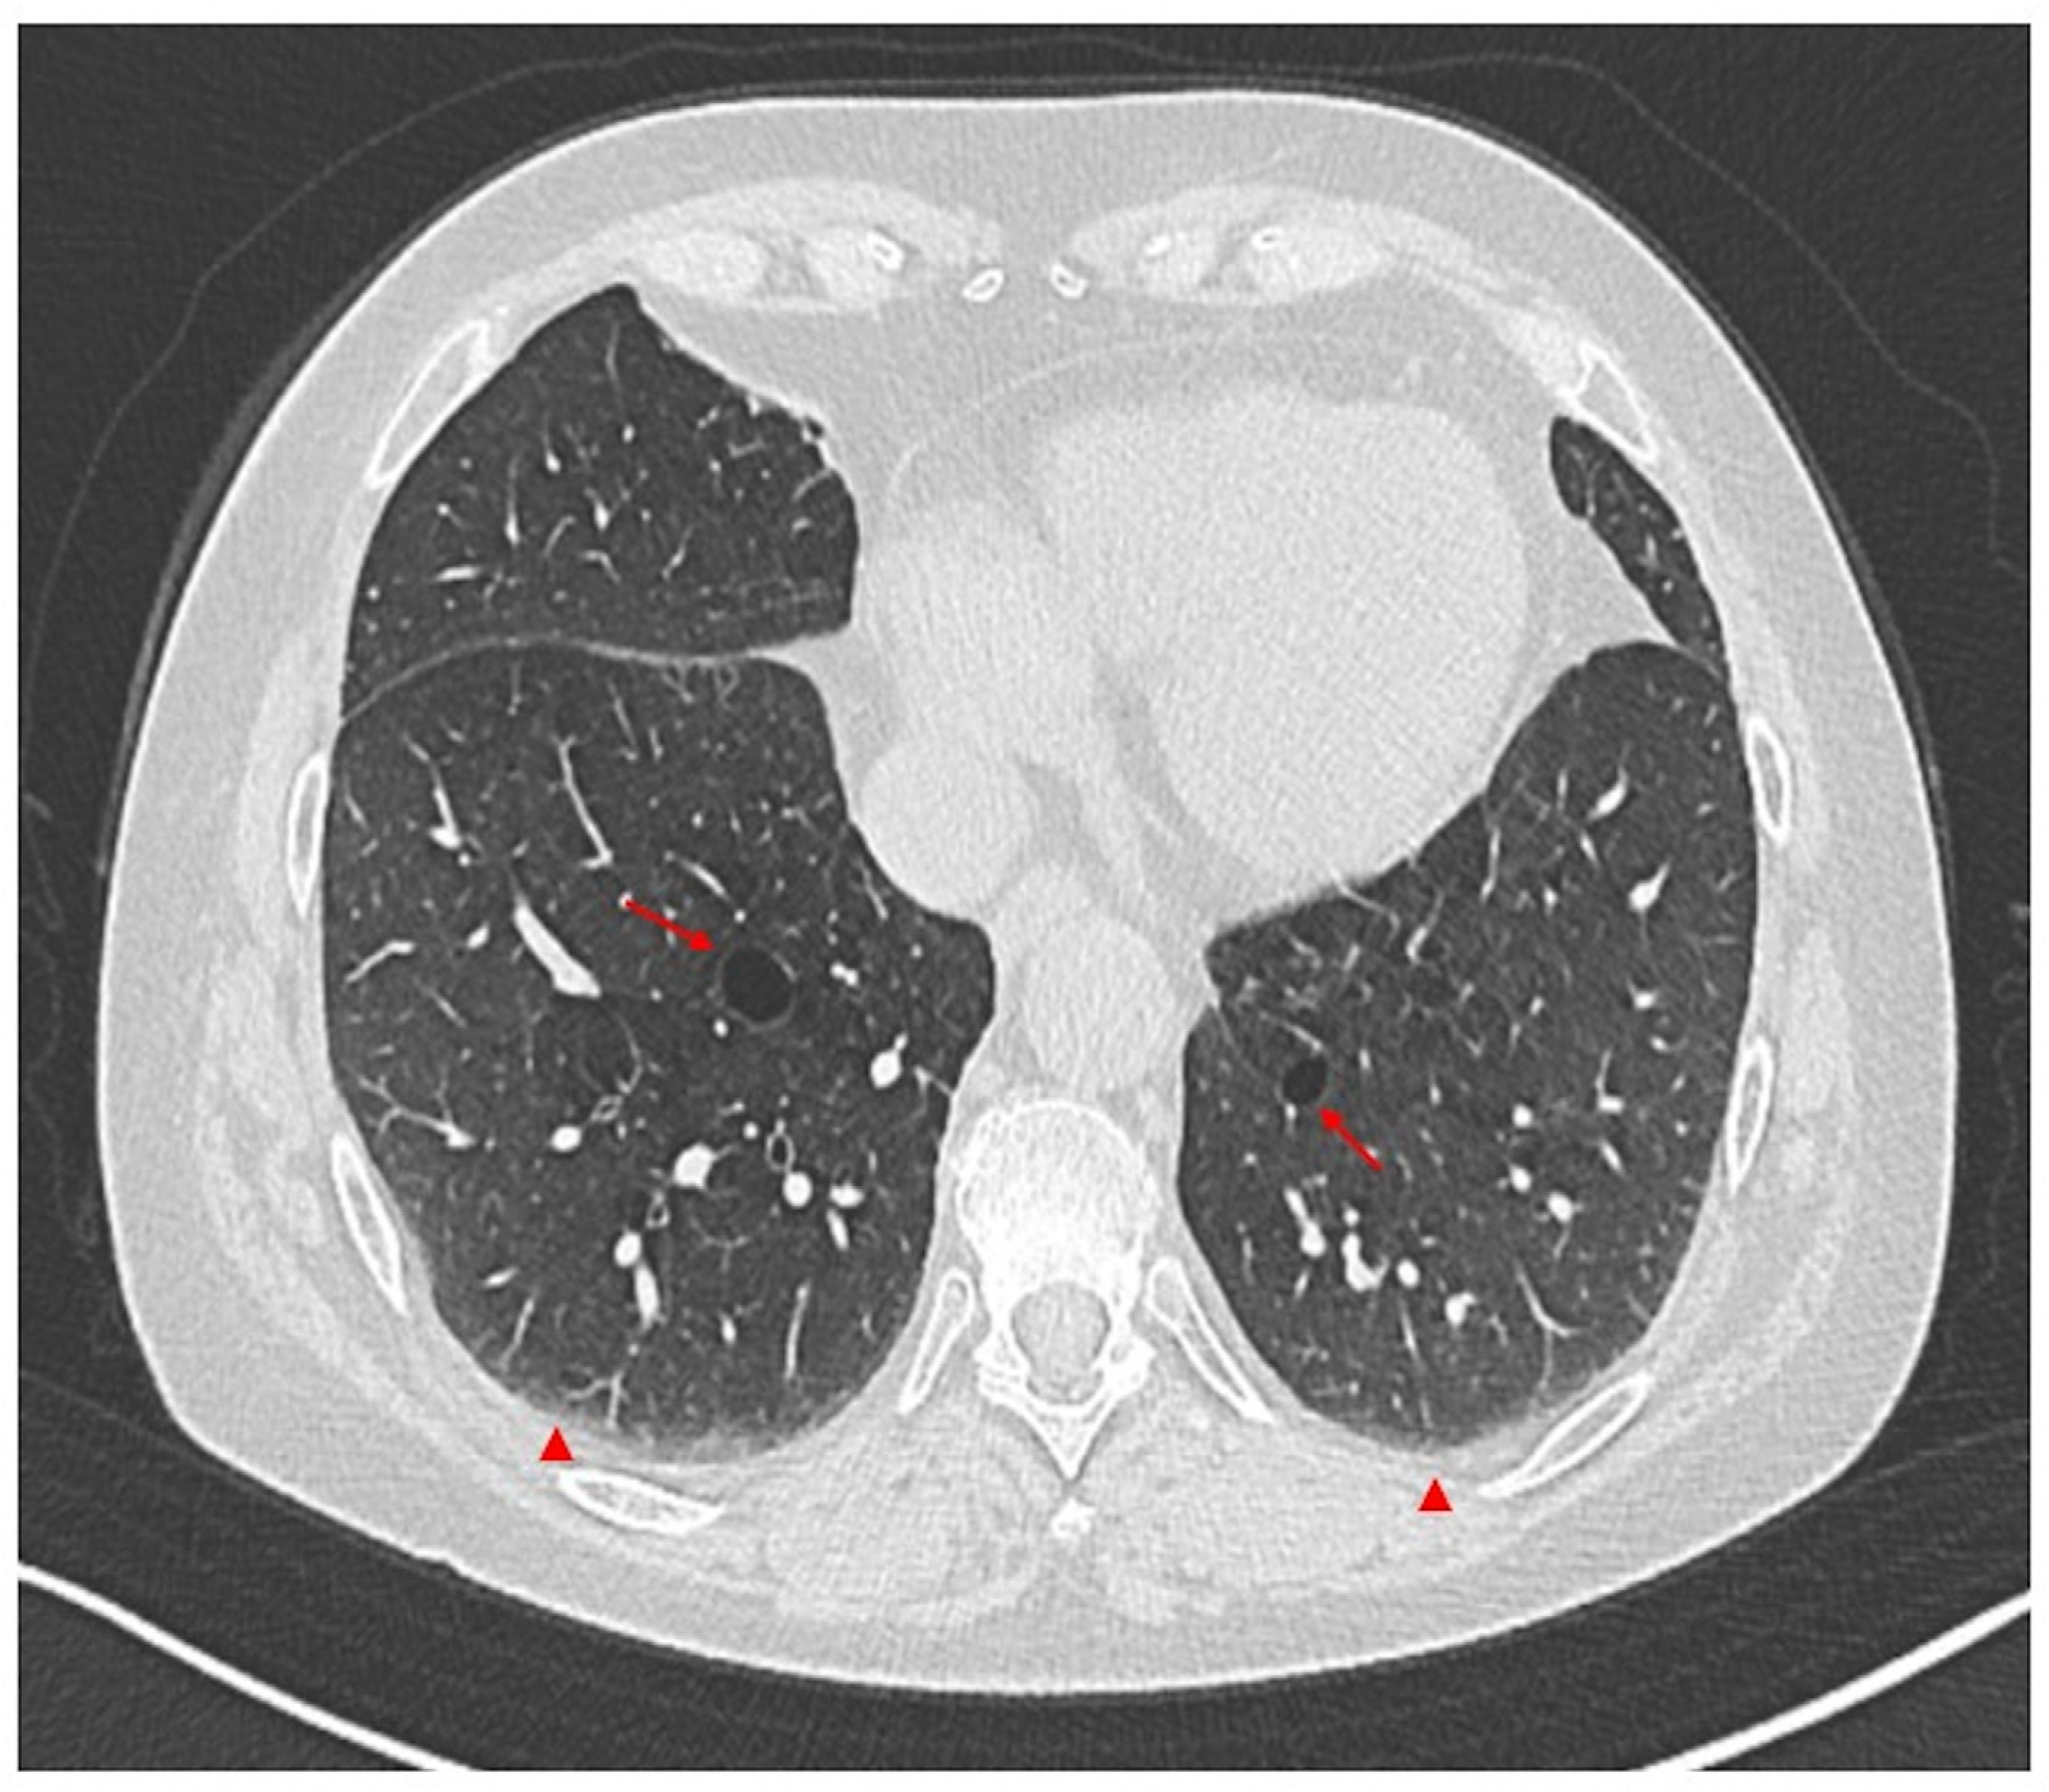

ILD in SLE usually runs asymptomatically, and this finding is incidental [29,50,54,73]. However, in other cases, symptoms may be initially mild and nonspecific, including dry cough, exertional dyspnea, and fatigue [18,38]. A physical exam may reveal inspiratory crackles during breathing, although fingernail deformities (clubbing) are uncommon. Lung function tests often reveal a restrictive pattern, characterized by a decrease in the DLCO (Figure 2) [29,73]. Le Tallec et al. [74] demonstrated a significantly higher prevalence of impaired DLCO among SLE patients, corroborating previous findings. They observed a strong association between reduced DLCO and severe clinical manifestations, including pleuritis, lymphadenopathy, and renal involvement. These results suggest that compromised DLCO may reflect widespread lung damage and be an early indicator of interstitial lung disease [74]. In diagnosing lung disease, HRCT plays a crucial role in identifying the lung involvement and characterizing the specific disease pattern (Figure 4).

Figure 4.

Axial non-contrast thorax computed tomography scan in a patient with systemic lupus erythematosus (SLE). The exam revealed abnormal permanent enlargement of the airspaces distal to the terminal bronchioles (arrows), accompanied by the destruction of the alveolar wall and subpleural interstitial involvement (arrowheads).

Studies reveal non-specific interstitial pneumonia (NSIP) to be the most common pattern observed on HRCT. However, usual interstitial pneumonia (UIP) is also observed in a significant number of cases [67,70,73]. The most frequent abnormal findings include ground-glass opacities, consolidation, honeycombing, and traction bronchiectasis [67,68,73].